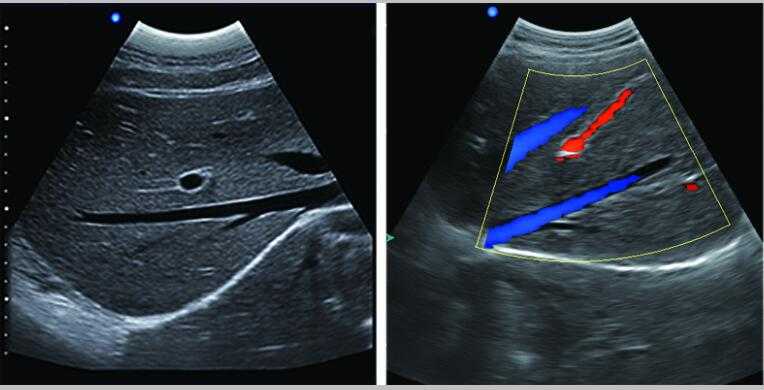

彩色多普勒

7.應(yīng)用:腹部、婦科、產(chǎn)科、心臟、血管和小器官、泌尿科、肌肉骨骼、兒科等